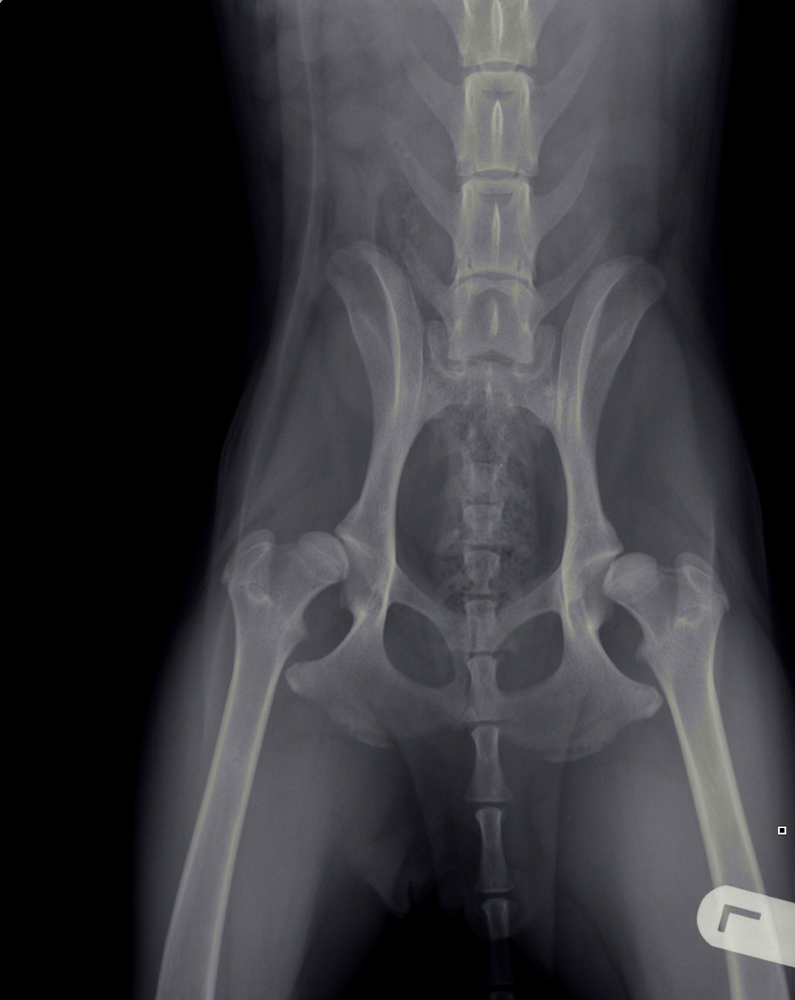

Heupdysplasie (HD)

Onder heupdysplasie wordt het volgende verstaan: een te ondiepe heupkom, waardoor de heupkop te veel ruimte heeft om te bewegen. Er is niet één enkele oorzaak voor te geven; meestal is het een combinatie van snelle groei, inspanning, voeding, leefomstandigheden en erfelijke factoren. Bij erfelijke factoren bestaat een aangeboren dysbalans tussen de spieren van het heupgewricht en de groei van bot, waardoor de heupkop niet goed in de kom wordt getrokken. Wat volgt is een abnormale ontwikkeling van het heupgewricht, wat kan leiden tot instabiliteit en daardoor irritatie van het gewrichtskapsel en het kraakbeen op de heupkop met artrose (=slijtage) als eindresultaat.

Artrose aan de heupen uit zich in het algemeen in bothaakjes aan de heupkop, verbreding van de hals van de heupkop (= de aansluiting van de heupkop met de rest van het dijbeen), onregelmatigheden in het bot van de heupkom en luxatie van de heupkop ten opzichte van de heupkom (heup geheel of gedeeltelijk uit de kom).

Met behulp van röntgenfoto’s kan de diagnose worden gesteld.

HD-foto’s en beoordeling door de Raad van Beheer

Het is mogelijk om rashonden op 12 of 18 maanden leeftijd te laten testen op heupdysplasie door het maken van röntgenfoto’s van de heupen (onder sedatie). Deze foto’s worden dan door de Raad van Beheer beoordeeld. Belangrijk is dat het stamboomnummer van het dier bekend is, evenals het chipnummer en de volledige (stamboom)naam van het dier.

HD-status

HD A (HD -)

Röntgenologisch vrij van heupdysplasie, dit betekent niet dat de hond geen drager kan zijn van de afwijking.

HD B (HD tc)

(Overgangsvorm) zijn geringe veranderingen passend bij heupdysplasie, maar die bij de fokkerij niet van belang te zijn.

HD C (HD ±)

(Licht positief) duidelijke veranderingen, passend bij het ziektebeeld van heupdysplasie.

HD D (HD +)

(Positief) duidelijke veranderingen, passend bij het ziektebeeld van heupdysplasie.

HD E (HD ++)

(Positief in optima forma) ernstige misvormingen van het heupgewricht.

De afwijkingen die op de röntgenfoto’s te zien zijn, komen niet altijd overeen met de last die de hond van deze aandoening heeft. Honden met aanmerkelijke afwijkingen zijn soms klachtenvrij, terwijl andere honden, met flinke pijn- of bewegingsklachten, soms slechts een beperkte afwijking op de röntgenfoto’s laat zien.